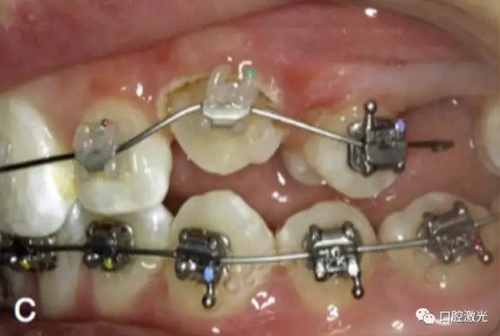

在近似理想位置粘接托槽

粘接托槽

3周后效果